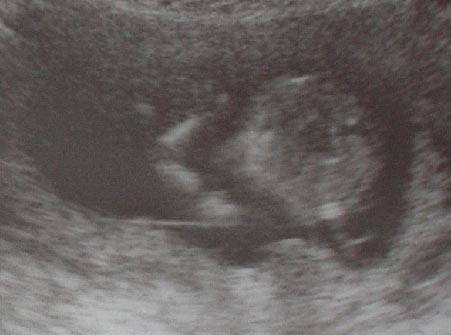

Das ist sehr unterschiedlich. Bei mir konnte man es diesmal in der 14ssw bereits sehen. Arzt wollte sich dennoch nicht festlegen. Durch eine FWU hab ich es dann aber schwarz auf weiß gehabt. Ich zeig dir mal das Bild aus der 14.ssw man sieht das Baby auf dem Bild von unten und links siehst du 2 weiße strichelchen am Körper. Davor das sind die Beinchen. Ist bei dem Orginal besser zu erkennen. So früh ist aber extrem selten. Bei meine, 2 Sohn sah man garnix, weil er immer ungünstig die beine zusammen gekniffen hat *g* Da wusste ich es nur vom Gefühl her, hab blau gekauft und dann gehofft, dass mein Gefühl mich nicht getäuscht hat *g* Meist kannst du etwa in der 17-20 ssw damit rechnen. lg. Anny